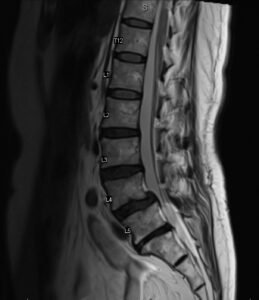

Как изглежда спондилолистезата на образно изследване

Спондилолистезата най-често се установява чрез образни изследвания като рентгенография или MRI. Тези изследвания позволяват да се види позицията на прешлените и дали има приплъзване между тях.

На рентген или MRI може да се наблюдава:

приплъзване на един прешлен спрямо друг

промени в междупрешленния диск

стеснение на пространството около нервните структури

дегенеративни промени в ставите на гръбначния стълб

Образните изследвания дават важна информация за структурата на гръбначния стълб, но винаги трябва да се интерпретират заедно със симптомите на пациента.